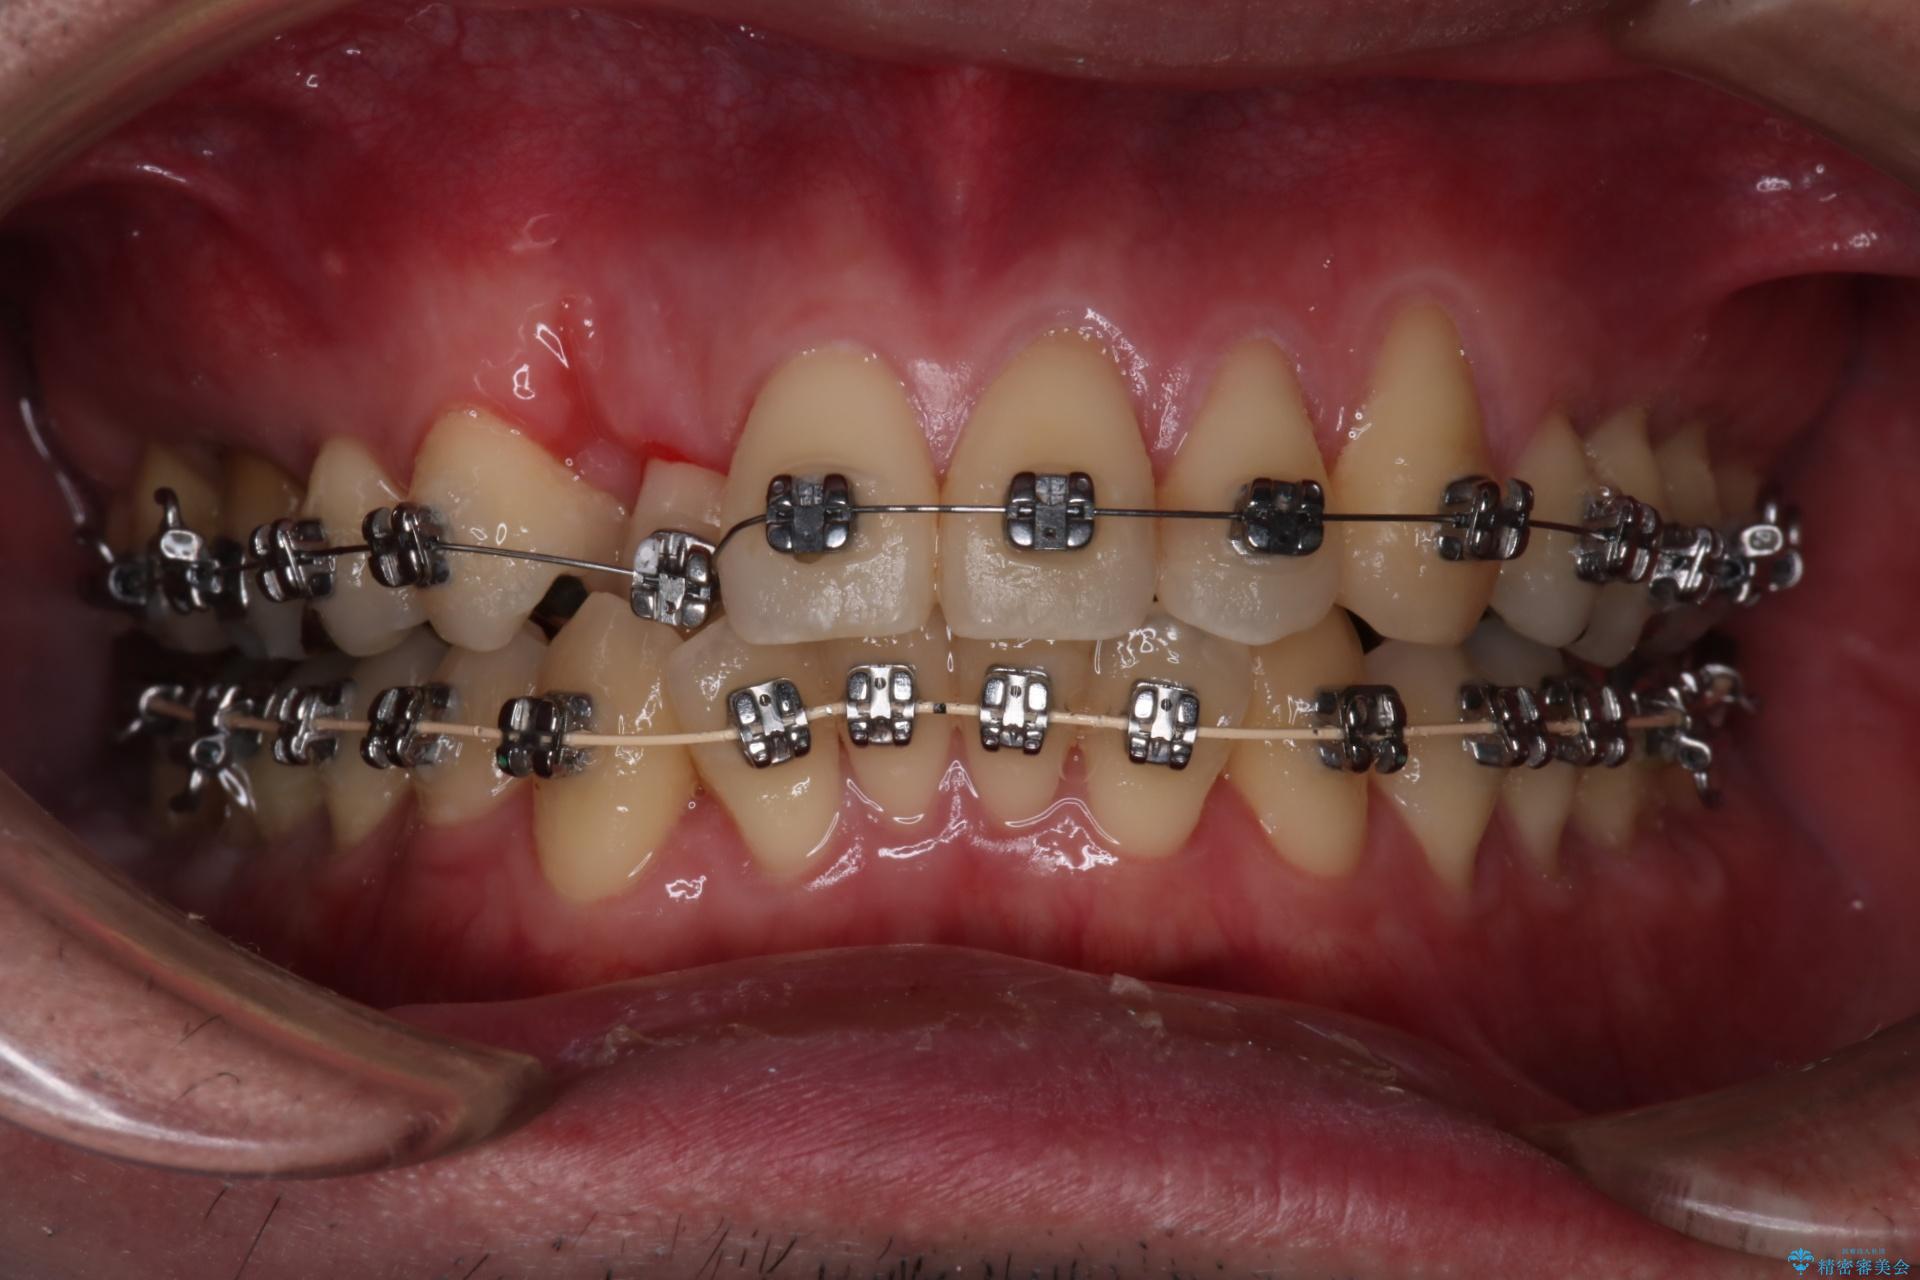

抜歯の本数を最小限に抑えたことで、治療計画も1年5ヶ月と短期間で終了することができ

主訴である前歯のがたつきも改善され綺麗な歯並びになりました。

矯正の装置を除去したタイミングで、ホワイトニングも行うことで歯の色味も白くなりました。